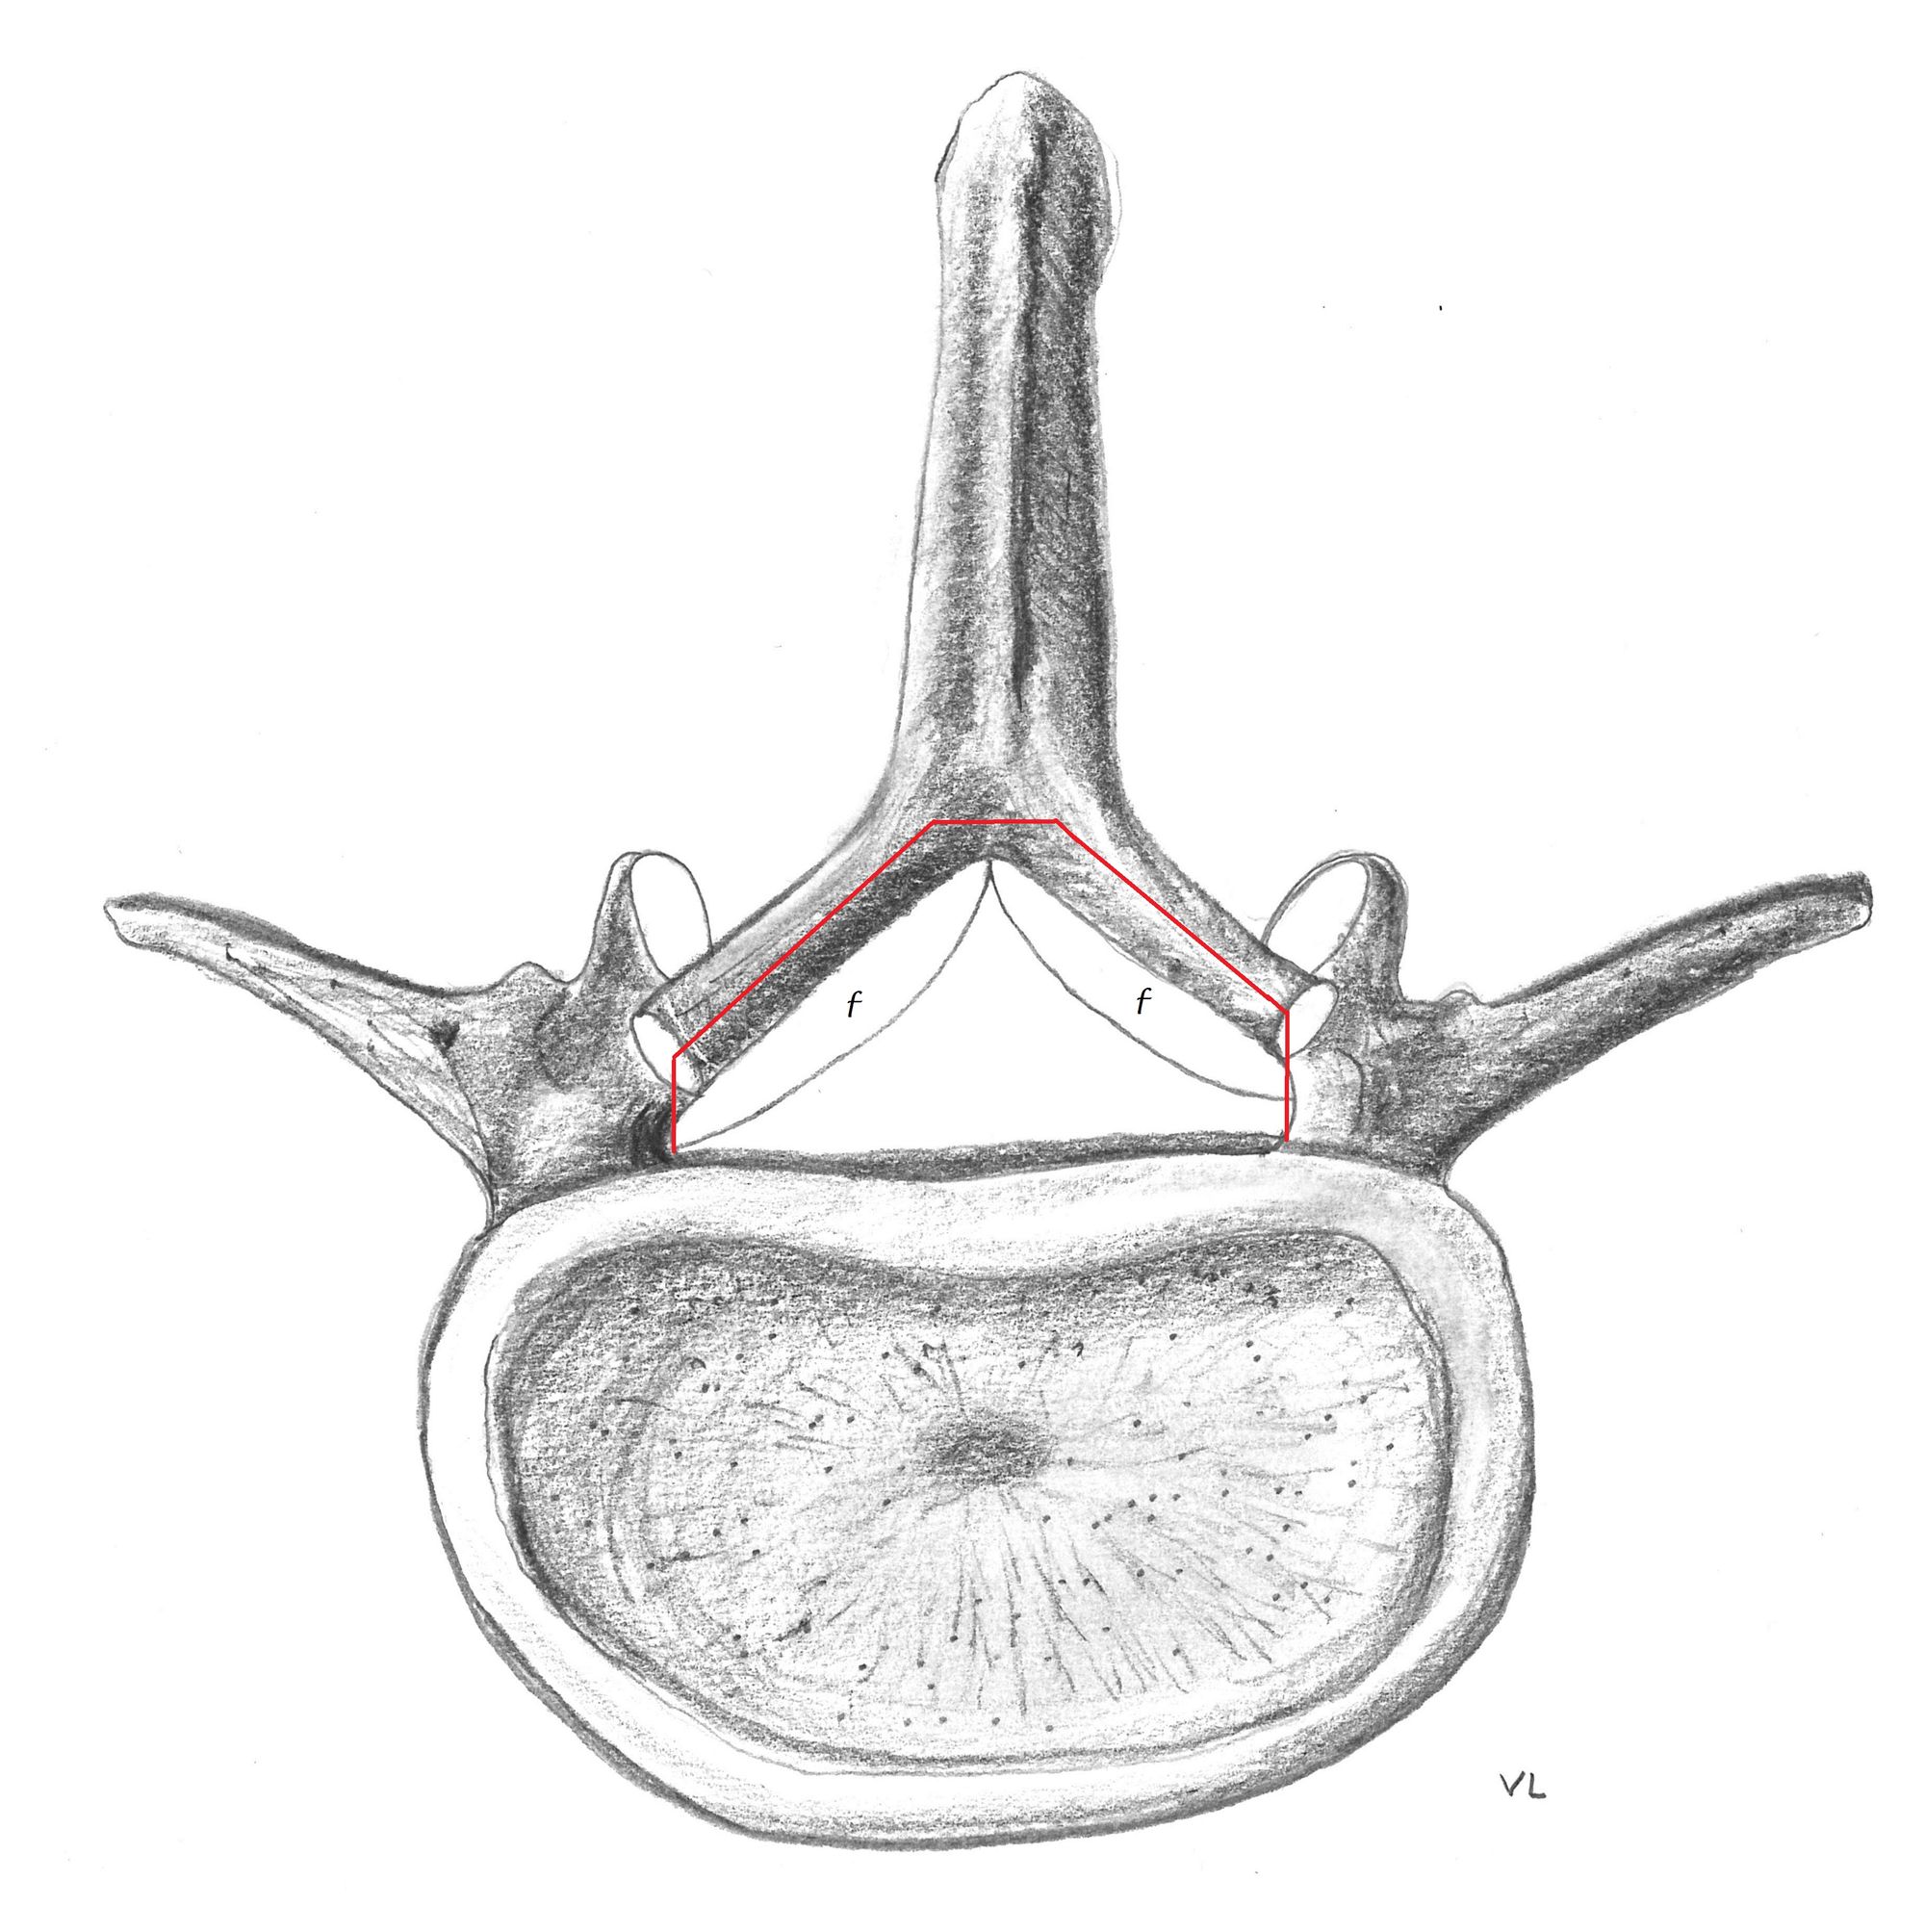

The inferior quarter of the inferior facet joint processes subjacent to the compressed level is resected using an osteotome using a strictly transverse osteotomy cut (Fig. 3).

Sublaminar osteotomy (Figs. 4a & 4b):

We perform the sublaminar osteotomy by passing the osteotome through the enlarged interlaminar space.

The first cut is paramedian and parallel to the target lamina. The chisel is directed into the cancellous bone of the lamina, between its lateral and medial (intraspinal) cortex, keeping the blade edge horizontal. The lamina is thus cut into two halves through its middle (Figs. 5 & 6).